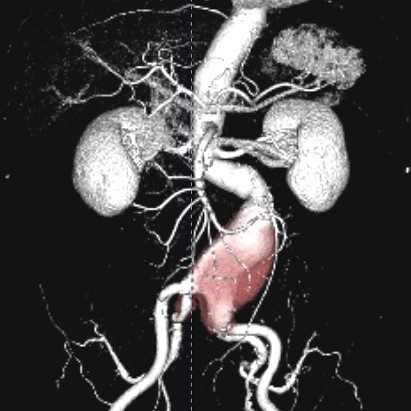

胸腹部血管撮影

胸腹部の血管撮影では、カテーテルを用いて大動脈や大静脈などの太い血管や、そこから分岐している細かい血管を選択的に造影して撮影を行います。心臓血管外科では大動脈瘤に対するステントグラフト治療(EVAR、TEVAR)、消化器内科では肝細胞癌の肝動脈化学塞栓術(TACE)、や門脈圧亢進症の静脈瘤の治療(B-RTO)などが行われています。またハイブリット手術室では、重症の大動脈弁狭窄症に対する経カテーテル大動脈弁植込み術(TAVI)が行われています。

腹部大動脈瘤術前CT

大動脈造影 ステントグラフト内挿術後

術後レントゲン写真